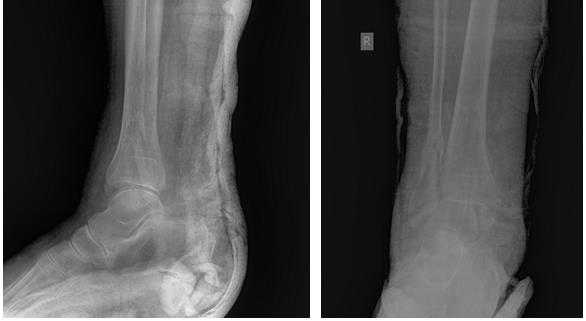

С целью уточнения диагноза проводится рентгенографическое исследование голеностопного сустава и стопы в прямой и боковой проекциях; в ряде случаев, с целью получения наиболее достоверных данных о степени разрушения таранной кости и голеностопного сустава, показаны рентгено-компьютерная, а также магнитно-резонансная томографии.

По достижении обезболивающего эффекта производится закрытая ручная репозиция перелома таранной кости с устранением грубых смещений отломков. При этом особое значение мы придаем устранению ротационного смещения переднего отломка таранной кости. С этой целью передний отдел стопы переводится в положение умеренной пронации. Затем в большеберцовую кость, на уровне ее нижней трети, вводят два винта Шанца и проводят спицу, которые закрепляют в кольцевой (или кольцевых) опоре аппарата. Через пяточную кость, перпендикулярно сагиттальной плоскости, проводят две спицы и закрепляют в заднем полукольце замкнутой опоры. Через кости среднего отдела стопы, не нарушая ее поперечного свода, проводятся две перекрещивающиеся спицы, которые закрепляются в переднем полукольце той же опоры. Опоры соединяются между собой резьбовыми стержнями с шарнирами. Перемещением по резьбовым стержням осуществляют дозированную дистракцию, поворотом переднего полукольца замкнутой опоры по шарнирам в направлении пронации переднего отдела стопы производят репозицию перелома таранной кости. При значительных по величине смещениях таранной кости производится открытая репозиция из малых операционных доступов с устранением всех видов смещений под визуальным контролем. По завершении репозиции, изолированно, через каждый отломок таранной кости проводят спицы, которые закрепляют в кронштейнах, установленных на замкнутой опоре. Операция завершается контрольной рентгенограммой голеностопного сустава в двух стандартных проекциях и рентгенограммой стопы в проекции на таранную кость. Срок лечения в аппарате составляет 2,5-3 месяца.

Рентгеновский контроль голеностопного сустава проводится перед выпиской из стационара и затем 1 раз в месяц с обязательным осмотром пациента в отделении. Вопрос об удалении спиц и винтов, демонтаже и снятии аппарата решается индивидуально, на основании данных клинико-рентгенологического обследования пациентов.